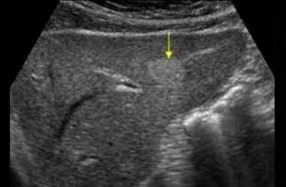

1.肝血管瘤

体检超声报告中此“瘤”非彼瘤(图1)

看到“瘤”字,千万不要惶恐,这是一种良性疾病,其发生自发破裂,比中500万大奖的几率还要低。因此,只有当肝血管瘤超过10公分以上,压迫到周围组织器官,才考虑手术治疗。